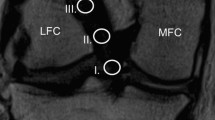

The proximal ACL graft underwent a significant MRI signal change from 6 weeks to 6 months after surgery and showed the highest signal intensity at this time point (p < 0.001). The APR subsequently declined to approximate the APR of a native proximal ACL at 1 and 2 years. The proximal APR was significantly lower than a native ACL at 6 weeks (p < 0.001) and higher at 6 months (p < 0.05) after surgery.

Similarly, the APR of the mid-substance ACL graft ran through a significant transformation from 6 weeks to 2 years postoperatively. While the APR 6 months after ACL-R is significantly different from a native mid-substance ACL (p < 0.01), the APR after 1 and 2 years showed a similar MRI signal compared with a native ACL.

APR of the distal section of the ACL graft showed a significant rise within the first 6 months postoperatively (p < 0.05) before drop** gradually at 1 and 2 years. The APR of distal section of the ACL autograft was significantly lower than the native ACL at all time points except from 6 months postoperatively (all p < 0.01).

AMR measurements

The AMR of the ACL autograft over the postoperative period is shown in Fig. 2B. The AMR changed significantly at the proximal (p < 0.001), mid-substance (p < 0.001), and distal (p < 0.05) part of the ACL graft.

AMR of the proximal ACL portion rose significantly from 6 weeks to 6 months (p < 0.001) after surgery and was by then significantly different to a native ACL (p < 0.001). Subsequently, the AMR started to decline to reach a similar AMR of the native proximal ACL at 1 and 2 years.

The mid-substance AMR increased significantly from 6 weeks to 6 months postoperatively (p < 0.001) before decreasing at 1 year and 2 years postoperatively (p < 0.01). The AMR was significant higher at 3- and 6 months after ACL-R compared with a native ACL (p < 0.001) but was not different from a native mid-substance ACL at 1 and 2 years.

The distal AMR rose significantly between 6 weeks and 6 months postoperatively (p < 0.05). It then dropped slowly to the lowest AMR at 2 years postoperatively. AMR of the distal intraarticular graft section was significantly lower than a native ACL at 2 years after surgery (p < 0.05, Fig. 3).